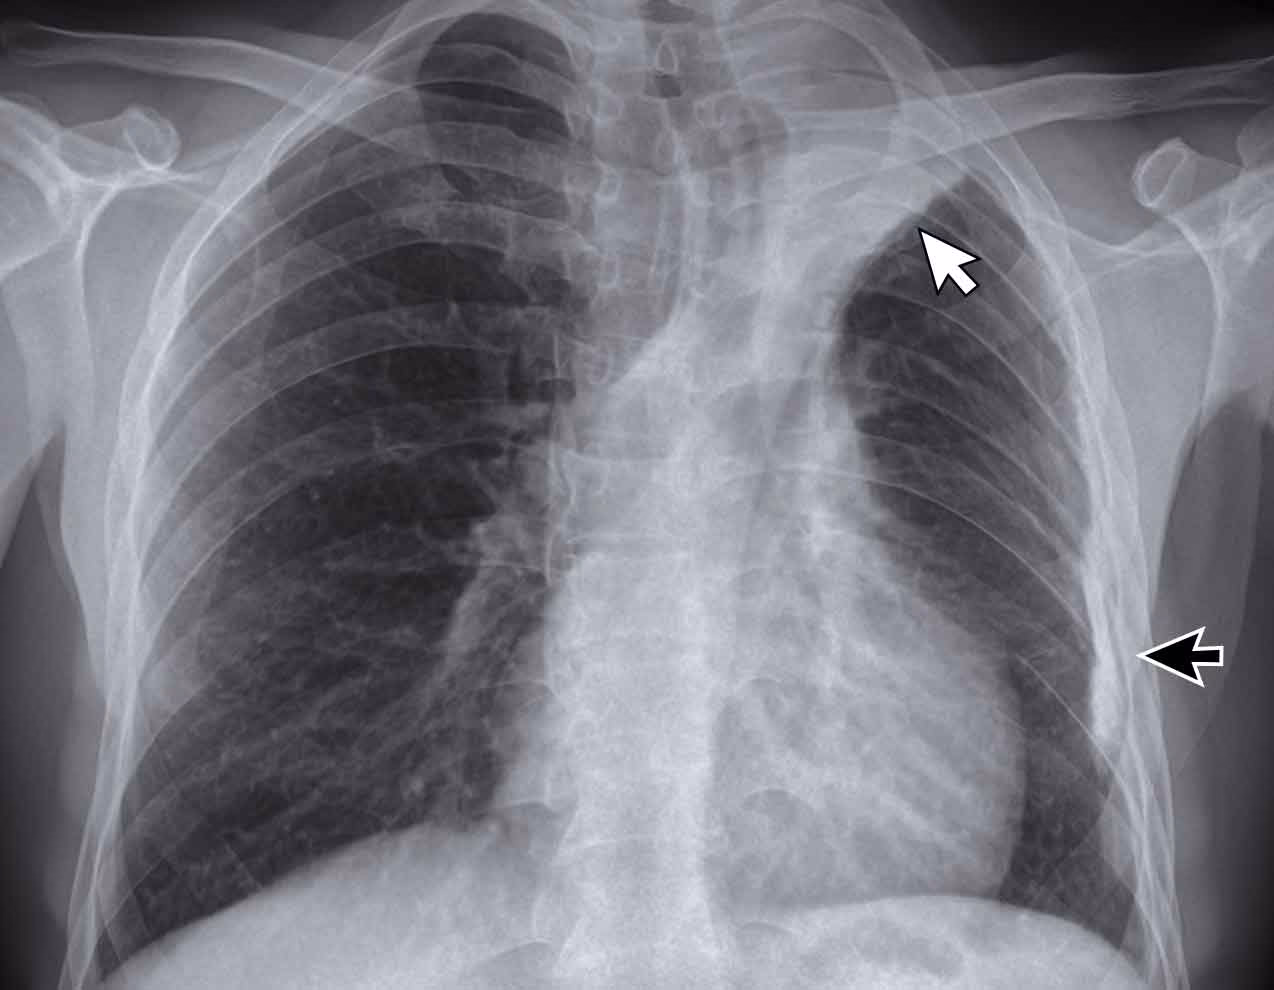

Når en læge har mistanke om aktiv tuberkulose, enten på grund af symptomer eller en positiv hud- eller blodprøve, er en røntgenundersøgelse af brystkassen ofte det næste skridt. Røntgenbilleder giver et visuelt indblik i lungernes tilstand. Når TB-bakterier vokser og spreder sig i lungevævet, skaber de betændelse og skader, som kan ses på et røntgenbillede. Disse forandringer fremstår typisk som unormale skygger eller pletter i områder af lungerne, der normalt er klare og gennemsigtige.

De klassiske tegn, en radiolog leder efter, er hvide eller grålige pletter, kendt som noduler (små, runde skygger) eller masser (større skygger). Disse indikerer områder med betændelse eller arvæv forårsaget af kroppens reaktion på bakterierne. En af de mest karakteristiske observationer ved TB er, at disse forandringer ofte findes i de øverste dele (apikale lapper) af en eller begge lunger.

- Kaviteter: I nogle tilfælde kan infektionen nedbryde lungevævet og skabe hulrum, kendt som kaviteter. Disse ses som mørke områder omgivet af en tyk, hvid væg og er et stærkt tegn på aktiv og smitsom TB.

- Hævede lymfeknuder: Lægen kan også se efter hævede hilære lymfeknuder. Disse lymfeknuder er placeret nær hilum, det centrale område i lungen, hvor luftrør og blodkar træder ind. Hævelse her kan indikere, at infektionen har spredt sig.

- Pleuravæske: Tuberkulose kan forårsage en ophobning af væske i rummet mellem lungerne og brystvæggen. Dette kaldes pleuravæske og ses som en ensartet hvid skygge, typisk i bunden af lungen.